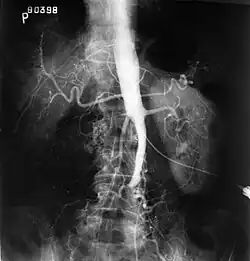

Fluoroscopic image of an aorta affected by Leriche's syndrome

Angiography provides important information regarding the perfusion and patency of distal arteries (e.g. femoral artery). The presence of collateral arteries in the pelvic and groin area is important in maintaining crucial blood flow and lower limb viability. However, angiography should only be used if symptoms warrant surgical intervention.[2]